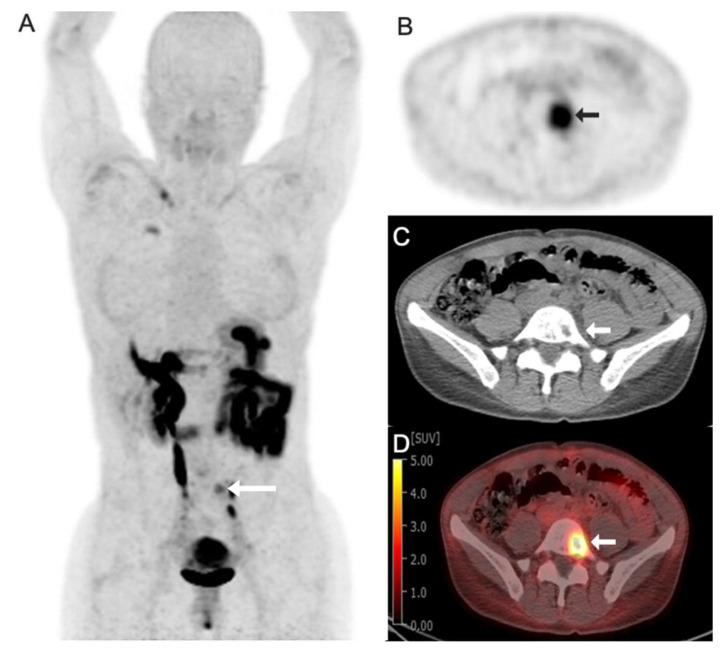

Targeted radioligand therapy (RLT) is an emerging field in anticancer therapeutics with great potential across tumor types and stages of disease. While much progress has focused on agents targeting somatostatin receptors and prostate-specific membrane antigen (PSMA), the same advanced radioconjugation methods and molecular targeting have spurred the development of numerous theranostic combinations for other targets. A number of the most promising agents have progressed to clinical trials and are poised to change the landscape of positron emission tomography (PET) imaging. Here, we present recent data on some of the most important emerging molecular targeted agents with their exemplar clinical images, including agents targeting fibroblast activation protein (FAP), hypoxia markers, gastrin-releasing peptide receptors (GRPrs), and integrins. These radiopharmaceuticals share the promising characteristic of being able to image multiple types of cancer. Early clinical trials have already demonstrated superiority to F-fluorodeoxyglucose (F-FDG) for some, suggesting the potential to supplant this longstanding PET radiotracer. Here, we provide a primer for practicing radiologists, particularly nuclear medicine clinicians, to understand novel PET imaging agents and their clinical applications, as well as the availability of companion targeted radiotherapeutics, the status of their regulatory approval, the potential challenges associated with their use, and the future opportunities and perspectives.

靶向放射性配体疗法(RLT)是抗癌治疗领域中一个新兴的领域,在各种肿瘤类型和疾病阶段都具有巨大潜力。虽然许多进展都集中在靶向生长抑素受体和前列腺特异性膜抗原(PSMA)的药物上,但同样先进的放射性缀合方法和分子靶向技术也推动了针对其他靶点的众多诊疗组合的开发。一些最有前景的药物已进入临床试验阶段,并有望改变正电子发射断层扫描(PET)成像的格局。在此,我们展示了一些最重要的新兴分子靶向药物的最新数据及其典型临床图像,包括靶向成纤维细胞活化蛋白(FAP)、缺氧标志物、胃泌素释放肽受体(GRPr)和整合素的药物。这些放射性药物具有能够对多种类型癌症进行成像的良好特性。早期临床试验已经证明,其中一些药物相对于F-氟脱氧葡萄糖(F-FDG)具有优势,这表明它们有可能取代这种长期使用的PET放射性示踪剂。在此,我们为执业放射科医生,尤其是核医学临床医生提供一份入门指南,以帮助他们了解新型PET成像药物及其临床应用,以及配套靶向放射治疗药物的可用性、监管批准状况、使用相关的潜在挑战以及未来的机遇和前景。